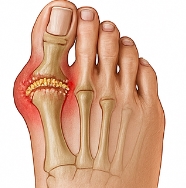

통풍 증상 중 가장 대표적인 것은 관절 부위의 극심한 통증과 붓기입니다. 대개 밤이나 새벽에 갑자기 찾아오며, 통증이 너무 심해 이불이 닿기만 해도 견디기 힘든 수준입니다. 통풍 증상은 주로 엄지발가락에서 시작하지만, 발목·무릎·손가락 등 다른 관절로도 퍼질 수 있습니다. 초기에는 2~3일 후 통증이 가라앉지만, 재발을 반복할수록 통증 기간이 길어지고 염증이 심해집니다.

② 관절 부위의 열감 및 홍조

통풍 증상에서는 통증뿐 아니라 열감과 붉은 피부색 변화가 동반됩니다. 염증이 심해지면 해당 부위의 온도가 올라가고, 손으로 만지면 뜨겁게 느껴집니다. 통풍 증상은 염증 반응이 활발할 때 발목, 발등, 손가락 관절 등이 붉고 붓는 양상으로 나타납니다.

⑤ 통풍 결절(토피) 형성

통풍이 장기화되면 요산 결정이 피부 밑에 뭉쳐 ‘토피(Tophi)’라는 덩어리가 생깁니다. 통풍 증상이 오랫동안 지속된 환자에게 자주 나타나는 현상이며, 주로 귀, 팔꿈치, 발등, 손가락 관절 주변에 생깁니다. 크기가 커지면 통증뿐 아니라 외형 변형까지 초래합니다.

통풍 증상을 장기간 방치하면 관절이 점차 변형되고 기능이 떨어집니다. 요산 결정이 관절 연골을 손상시켜 관절의 구조적 변형이 일어나며, 심한 경우 걷기나 손동작이 어려워질 정도로 기능 장애가 생깁니다. 통풍 증상이 반복되면 연골뿐 아니라 뼈와 인대까지 침범할 수 있습니다.